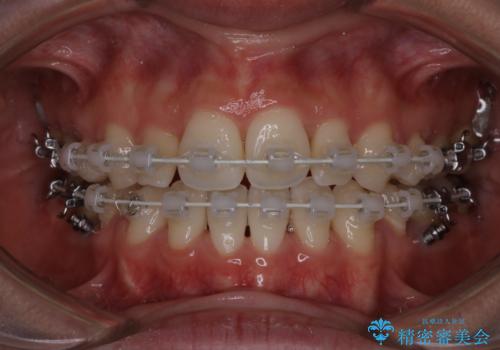

- 口元をさげたいという主訴で来院されました。4番の歯を4本抜歯し、遠心移動とIPRをしました。右上2番が矮小歯のため見た目を重視するならクラウンの提案をしましたが、そのままでの治療を希望されました。

矯正治療の最終段階でスペースクローズにやや時間がかかりましたが、前歯が下がったことで口元の位置も下がりきれいになりました。